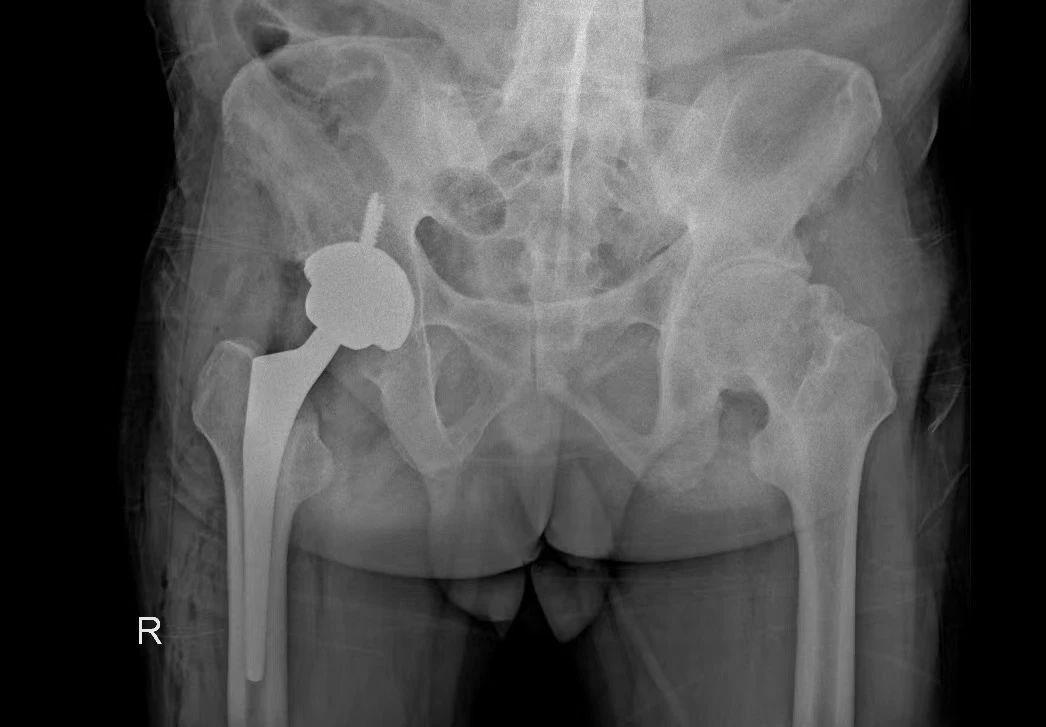

術(shù)后平片

術(shù)后,在科室醫(yī)護(hù)人員及康復(fù)團(tuán)隊(duì)的精心照料下,患者術(shù)后12小時(shí)可以下地走路,術(shù)后一周棄拐行走恢復(fù)良好并順利康復(fù)。

術(shù)中,DAA入路充分顯露髖臼,順利注冊(cè)好標(biāo)記點(diǎn),機(jī)械臂精準(zhǔn)地定位到預(yù)期規(guī)劃位置,輔助完成髖臼的磨銼和髖臼杯放置,羅軍主任與手術(shù)團(tuán)隊(duì)成員參照術(shù)前規(guī)劃,協(xié)同機(jī)器人“作戰(zhàn)”,對(duì)髖臼窩進(jìn)行了亞毫米級(jí)的精確磨銼,將髖臼杯的安裝角度控制到了1°以內(nèi),達(dá)到了精確的效果,手術(shù)圓滿完成。